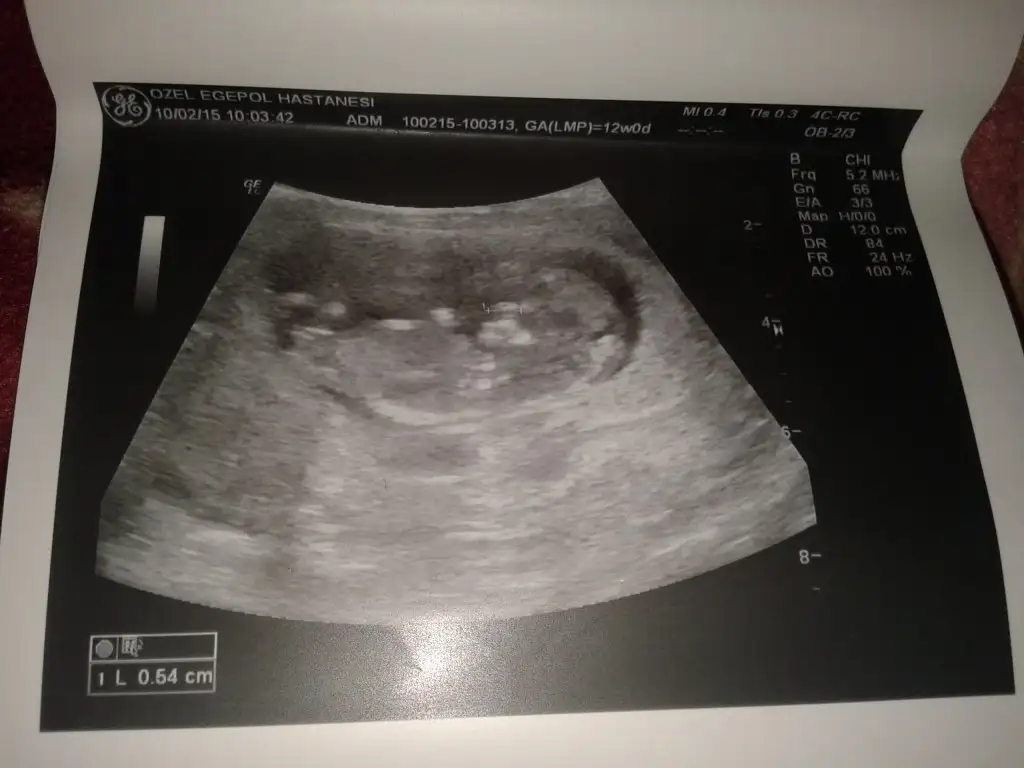

Kizlar mrb. Oncelikle hepinize saglikli mutlu bir gebelik sureci diliyorum. Benim bugun 11. Haftam bitti cok sukur. Ekte 10+2 haftalik goruntusu var bebisimin. Nub teorisine gore cinsiyeti hakkinda yorum yapabilirmisiniz? Oncelikle saglikli olmasi tabiki temennimiz. Ama merak ettim iste:)

Eklentiler

• 10+2 haftalık.webp

2,1 KB · Görüntüleme: 131